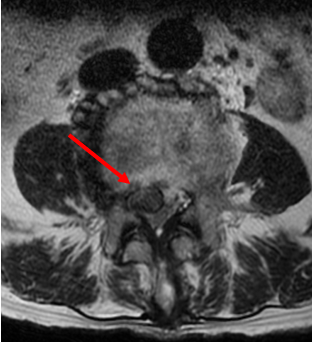

在家人陪同下,她来到了姜为民主任的门诊,在耐心地询问病史及细致的查体后,姜主任判断出这多半是“腰椎间盘突出”在作祟。腰椎磁共振检查结果也证实了他的诊断。

(巨大的椎间盘压迫神经)

对于椎间盘突出症,轻者可以采取保守治疗,但像王奶奶这样的巨大椎间盘突出,症状又非常严重的,保守治疗很痛苦,手术治疗非常必要,由于岁数大,如果采取常规的开放手术创伤及风险都较大,因此,微创手术是最佳选择。在跟王奶奶及家属充分沟通后,姜主任团队为老人施行了一种简称为UBE的手术,术后效果立竿见影,困扰了王奶奶3个多月的症状消失了。